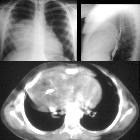

Role of

different imaging modalities in the evaluation of normal and diseased thymus. a Chest X-ray PA view shows a near-total opacification of the left hemithorax and right upper lung zone merging with the mediastinum. b Axial CT chest mediastinal window shows a large fat attenuating mass with thin hypodense fibrous septae. c MRI lung T1 WI shows the hyper-intense signal of the mass confirming its fatty nature. Imaging diagnosis and histopathologic assessment revealed “thymolipoma”